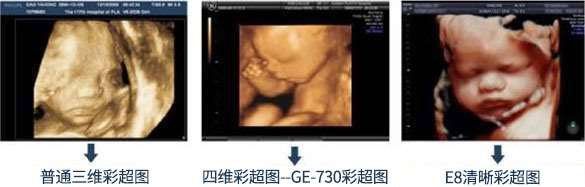

技术设备——引进美国GE设备

武汉百佳妇产医院引进多台美国GE超声筛查设备,该设备具有从二维到三维直至四维的专业功能,筛查、成像一步到位。

在360°立体观察宫内胎儿发育情况筛查的同时,还能清晰显示胎儿在宫内的动态,呈现宝宝在妈妈肚子里的各种动作神态,留下宝宝珍贵的0岁记忆。